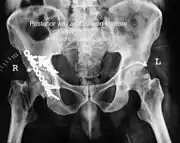

Acetabular fracture as seen on plain X-ray

1. Pelvis with both hips antero posterior view. This view shows six important landmarks of the acetabulum, specifically:

• Pelvic brim

• Ilio ischial line

• Tear drop

• Anterior wall

• Posterior wall

• Weight bearing dome